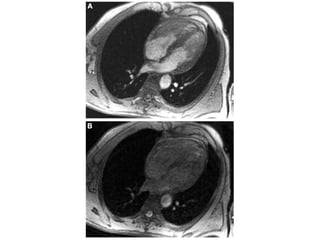

• #83 Renal failure progressive dyspnea on exertion. A, CMR reveals left ventricular hypertrophy with severe biventricular systolic dysfunction (four-chamber long-axis cine systolic image). B, Matching LGE imaging shows rapid washout of the contrast agent from the blood pool with diffuse intramyocardial LGE of the septum, subendocardial LGE of the inferior wall, and diffuse atrial LGE (black arrows). This pattern is consistent with amyloidosis.